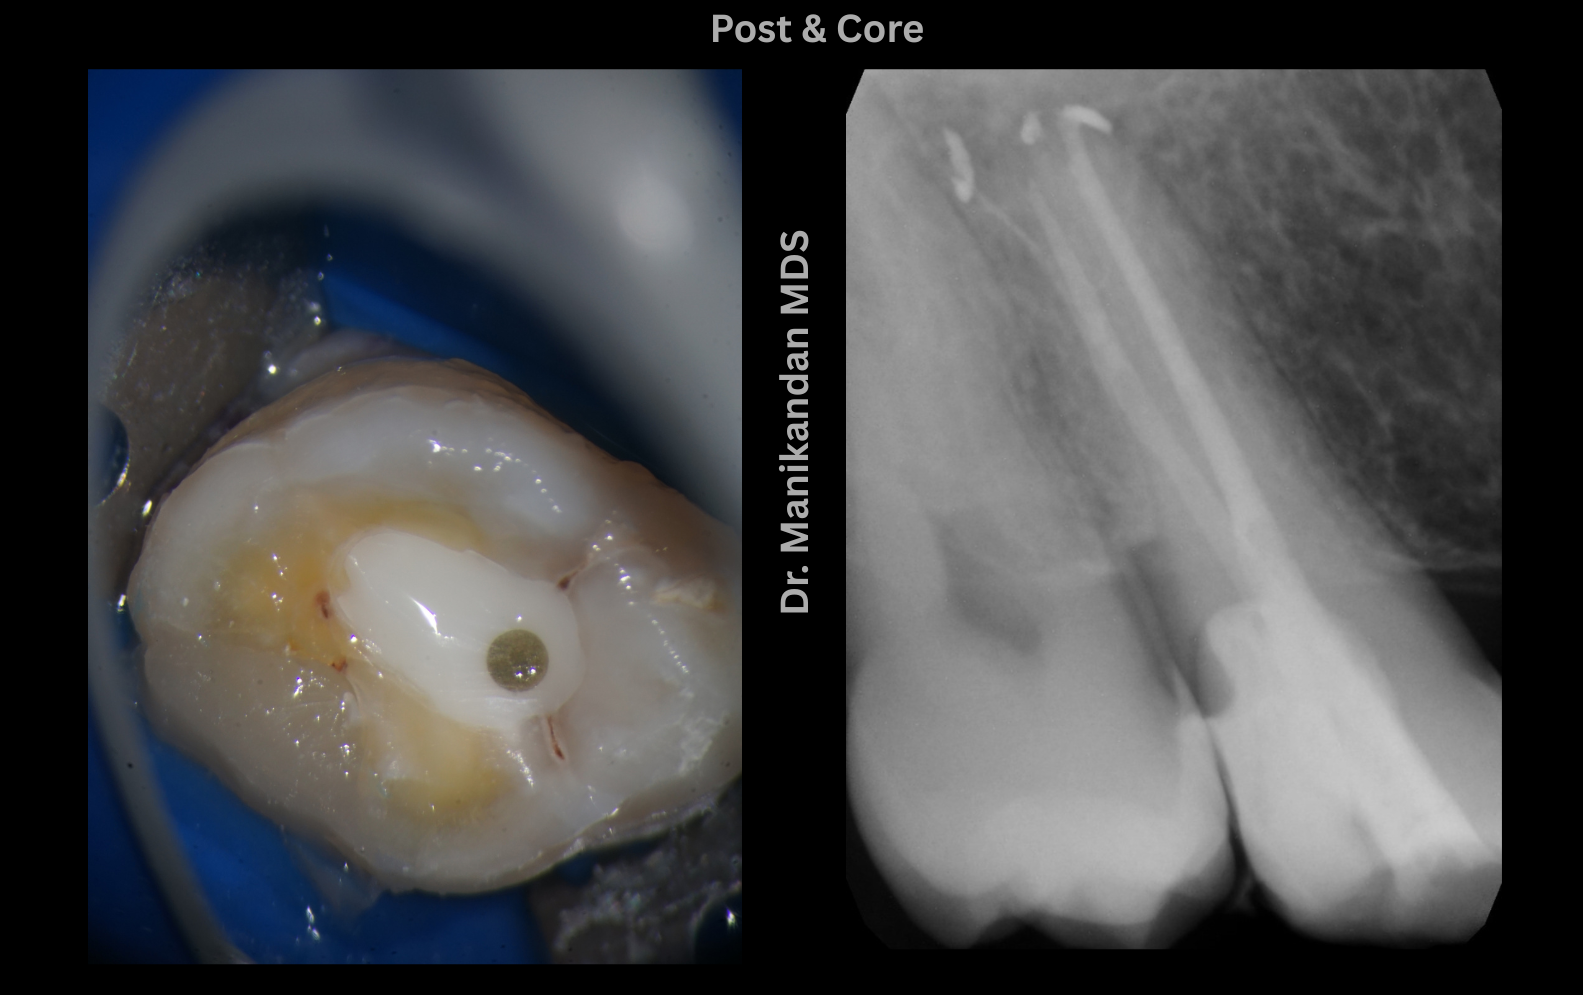

Our clinic specializes in Root Canal Treatment under a Microscope, a state-of-the-art procedure that ensures precision, comfort, and long-term dental health. Led by the highly experienced Dr. Manikandan, we bring expertise, advanced technology, and compassionate care to every root canal procedure.

With over 25 years of experience, Dr. Manikandan is a specialist in root canal therapy. His meticulous approach and expertise in microscope-assisted procedures ensure patients receive the best possible care. Known for his gentle techniques and attention to detail, Dr. Manikandan has built a reputation as one of the best dentists in Coimbatore.

Our clinic is equipped with the latest dental technologies, including high-powered dental microscopes, which enhance visibility and precision during root canal treatments. This ensures successful outcomes even for complex cases like curved or calcified canals.

Our modern dental microscopes allow detailed visualization of the root canals, ensuring thorough cleaning and sealing for optimal results.

We use advanced imaging technologies to assess the internal structure of the tooth, aiding in accurate diagnosis and treatment planning.